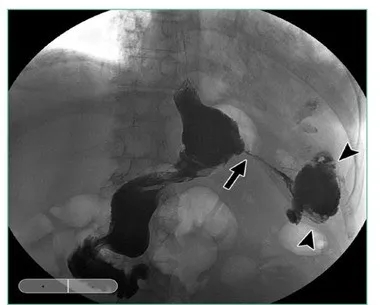

A leak from the SG portion of the procedure has historically been the most common area for a leak after a duodenal switch. The incidence has been reported as 1 to 4 percent, depending on the study evaluated. Over the last 5 to 10 years, the incidence has dropped as surgeon experience has increased in performing the SG as a stand-alone procedure. The most common area for a leak is in the upper one-third of the sleeve due to narrowing or stricture of the sleeve at the incisura angularis (Figure 2). This will cause an increase in pressure in the sleeve with a blowout at the upper portion of the staple line near the gastroesophageal junction since this is the weakest point in the sleeve. The treatment of a sleeve leak in the acute setting without a significant obstruction involves a washout of the affected area with resuturing or restapling of the sleeve. Many of these can heal completely if addressed early enough with minimal contamination. In the chronic setting or with a chronic fistula, it gets a bit more complicated. Nutritional support and antibiotics are required initially, combined with adequate drainage. Drains can usually be placed via a surgical approach or with the aid of interventional radiology, but recent studies have shown that drainage can also be facilitated with endoscopic techniques, such as an endoscopic wound vac or endoscopic septotomy. The most important aspect though for definitive treatment is to look for and relieve the obstructive point, which is usually at the angularis. This can be done with placement of an endoscopic stent, but in reticent cases, eventual surgical resection and Roux-en-Y reconstruction might be required.